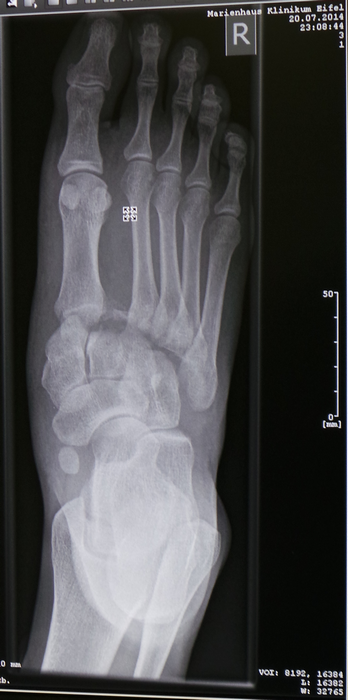

Aangekomen bij het ziekenhuis werden er foto's gemaakt. Resultaat:

- 4 middenvoetsbeentjes compleet uit de kom en mijn grote teen die toch ook niet helemaal stond zoals het hoorde.